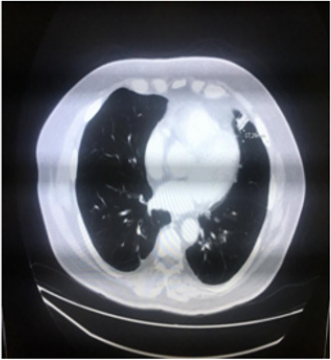

We describe a case of a 69-year-old male patient, diagnosed with malignant melanoma when he was 64. His co morbidities were systemic hypertension and dyslipidemia, and there was no family history of cancer. The primary lesion was located in his left arm and it was respected in February 2015. The histological analysis showed the lesion was completely removed with the following characteristics: Below 2.1 mm, vertical growth phase, Clark IV, mitotic index 9/10, no vascular invasion, ulceration present and margins free of malignancy - pT3b; immunopheno type BRAF wild-type. The initial procedure required a wider excision; this was performed two months later and there was no residual melanoma. At the same time the patient underwent a left axillary lymphadenectomy in which there was malignant involvement of one lymph node, of the sixteen removed. In December 2015 a chest computerized tomography (CT) scan showed a small nodule (18 mm) in his pulmonary ligulae (Figure 1). A positrons emission tomography (PET) scan confirmed this finding with a mild hyper metabolic activity (SUV 2.8); no other lesions were seen.

In March 2016 a transthoracic biopsy of this pulmonary nodule was performed and the microscope confirmed a metastatic melanoma. Although, in April 2016 (ten months since diagnosis) a new CT scan showed the nodule was smaller – 10 mm in the greatest diameter. Based on this unusual finding the patient was closely monitored and was clinically reviewed every 3 months by the surgical and oncological teams. The nodule continued regressing for the next months and in November 2016 a new chest CT showed no longer the lesion. In its place remained just a tissue resembling fibrosis. A new chest CT scan performed in October 2017 (22 months since the nodule was first seen) was totally normal (Figure 2). The patient persisted in follow-up and his last evaluation was in January 2020; he was healthy and without neoplastic symptoms